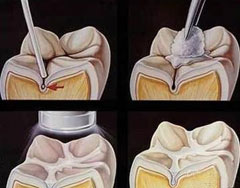

急性梗阻性化脓性胆管炎

疾病介绍:急性梗阻性化脓性胆管炎泛指由阻塞引起的急性化脓性胆道感染,是胆道外科病人死亡的最重要、最直接的原因,多数继发于胆管结石和胆道蛔虫症。发病基础…【详细】